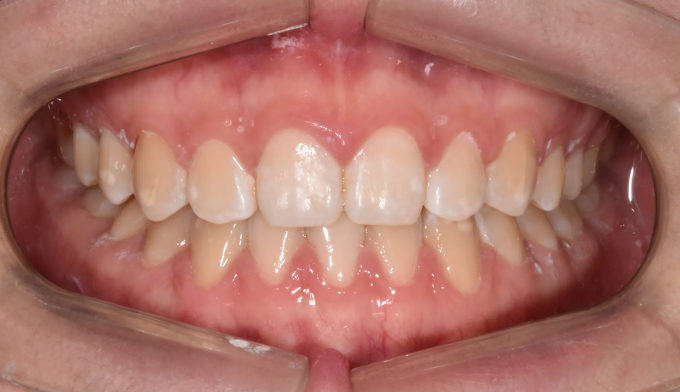

아래 앞니 하나가 선천적으로 부족한 경우이지만 주걱턱 경향으로 인해 아랫니가 윗니를 계속 자극하여 윗니까지 벌어진 케이스입니다. 윗니의 공간을 닫아주기 위하여 아래앞니를 먼저 후방이동시켜줬고, 이후에 벌어진 윗 앞니를 가지런하게 모아 마무리하였습니다. 아래앞니 하나가 부족하기때문에 위아래 가운데선을 맞추지 않고 종료하였습니다. 총 교정기간은 11개월입니다.